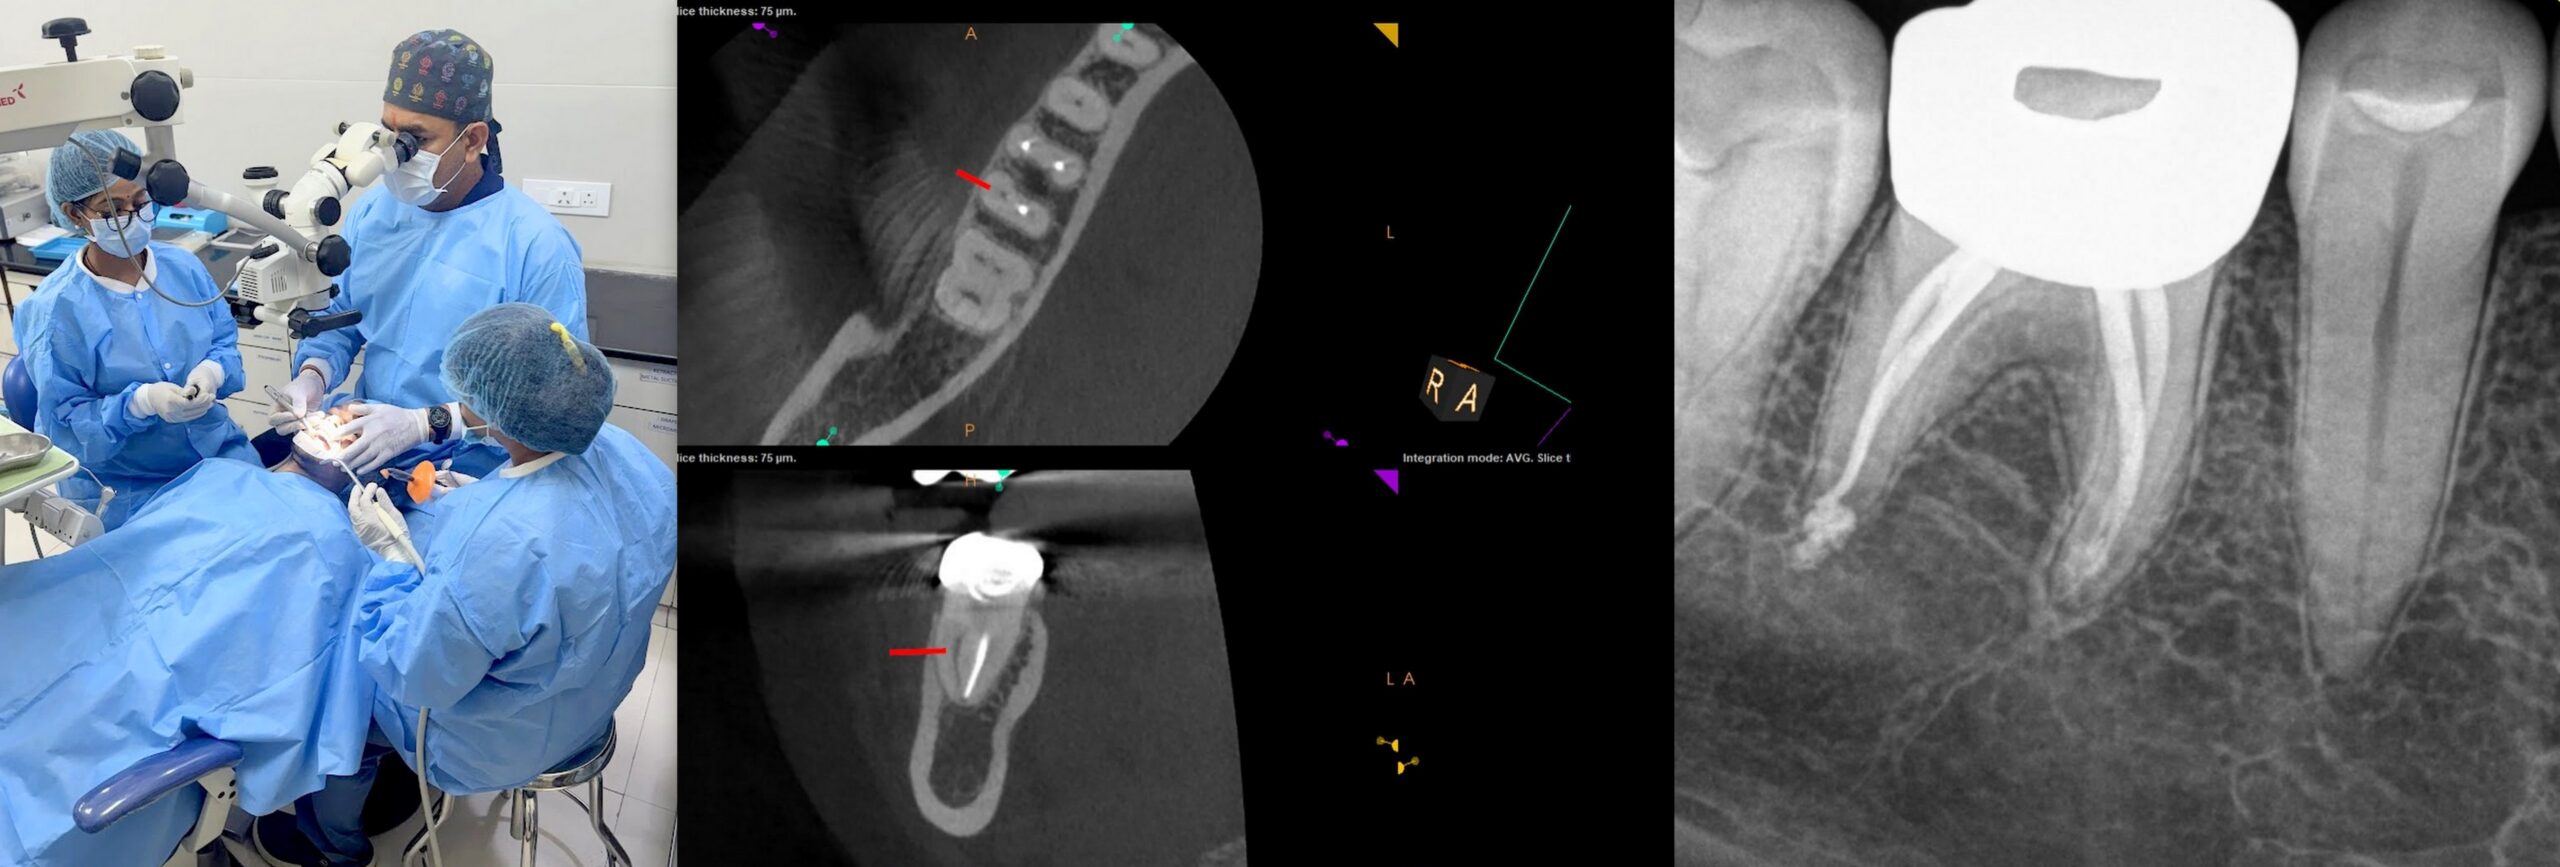

This clinical course will teach you all you need to setup an advanced endodontic practice. Step-by-step diagnosis process, case difficulty assessment, managing hard to anesthetize hot teeth, CT, and ultrasonic all are included. Learning cone beam CT scan indications and ultrasonic will help you with your diagnosis and treatment. Dental operating microscopes will form an integral part of teaching RCTs.

The practical module of the course will teach you how to find and negotiate the calcified canals, finding additional canals, as well as clean, shape, irrigate, and finally obturate the canals. This course will also cover the management of endodontic mishaps like broken instrument retrieval, reRCT, perforation repair and ledges bypass and management.